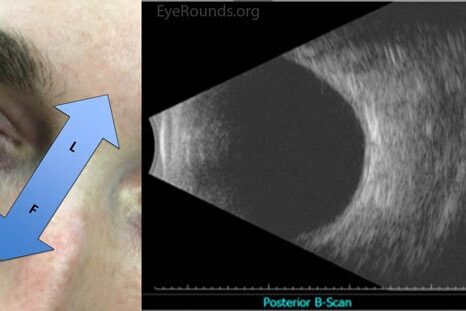

Oftalmologia este ramura medicinei care se ocupă cu diagnosticul și tratamentul bolilor oculare.

Oftalmologia este specialitatea care se ocupă cu depistarea, diagnosticarea, tratarea şi recuperarea bolnavilor cu afecţiuni ale globului ocular şi anexelor globului ocular. Cele mai frecvente tulburări includ cataracta, glaucomul, retinoaptia diabetică, stabismul, tumori oculare.

Examinarea oftalmologică periodică și completă face parte din îngrijirea primară regulată, deoarece multe boli oculare sunt silențioase și fără simptome.

În timpul examenului oftalmologic pot fi detectate potențiale boli de orbire, simptome oculare ale unei boli sistemice, tumori sau alte simptome ale anomaliilor cerebrale.

Evaluarea oftalmologică completă constă în examinarea externă a globului ocular, testarea acuității vizuale, examinarea funcției irisului, motilitatea extraoculară, acuitatea vizuală, presiunea intraoculară etc.